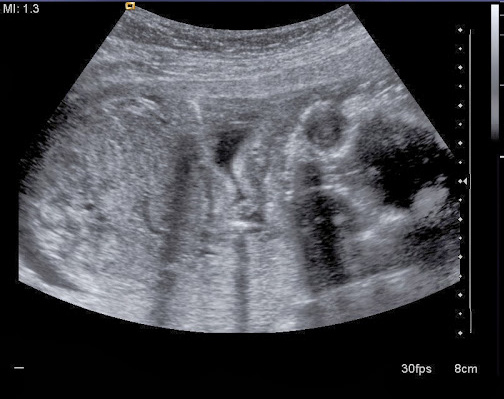

Šestý měsíc (25. týden)

Pro velký úspěch blonďatého projektu vám přinášíme druhé kolo našeho pupkatého příběhu :). A už je pěkně vykutálenej!

- kontroly a ultrazvuky jsme skrouhli na absolutní minimum

- víme ale, že by se nějaký mímo mělo narodit koncem března

- zatím vypadá akurátní velikosti i počtu končetin

- teď by mohlo mít kolem 30 cm a 600 gramů